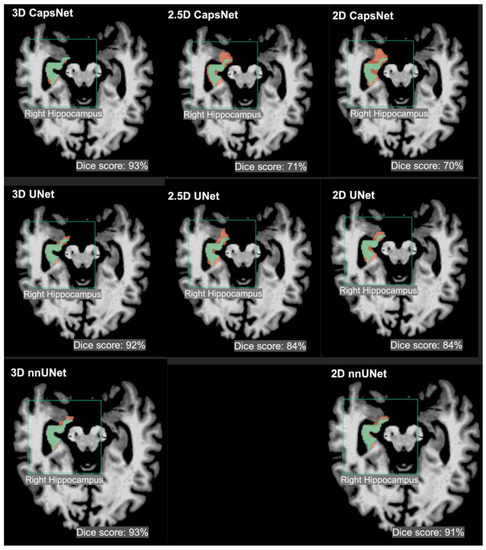

θcomplex3 eYecandy vs. θcomplex Same Brain, Different Look?—The Impact of Scanner, Sequenceの詳細情報

Same Brain, Different Look?—The Impact of Scanner, Sequence。Amazon.com: TheraSuva Total Eye Complex - Lutein + Bilberry。Comparing 3D, 2.5D, and 2D Approaches to Brain Image Auto。★プロフィールを一読下さい★・ぱんしょこと申します。アニメゲーム同人系CDを多数出品しています。よろしければフォローお願いいたします。・即購入→全商品可能です。・値下げ→全商品可能です。※一部例外あり★状態★・本商品についての状態は下記矢印以降に記入しております。→本商品はディスク面に目立った傷等なく、問題なく再生可能です。・当方出品物は当方がパソコンにて取り込みをしております。※ 動作確認は取り込み時に行っておりますので、CD再生は全商品可能となっております。・CDケースの状態につきましては、状態の記載に反映されておりません。※CDのディスク状態が反映されております。・商品の記載事項については、同一文面を使用しておりますため、少しでも気になる事がございましたら、必ずご質問くださいませ。例)ケース状態、商品付属物、ブックレート状態帯の有無、特典の有無、見にくい箇所など・全商品にテンプレート文章が反映されております※写真に写っている物のみが販売物となります。・下記ハッシュタグより当方出品CDのみがご覧いただけます。→ #ZAINのアニメCD達。Same Brain, Different Look?—The Impact of Scanner, Sequence。けむけむ (詳細コメント欄)。【新品未開封】Liella Club プレミアム盤 CD BD3枚 継続特典付。「強殖装甲ガイバー・スペシャル」 2枚組CD 初期OVA版のサントラです。ゾイドオリジナルサウンドトラック。THAT'S ATARI MUSIC ATARI GAMES 1 ゲームサントラ。遊戯王 SOUND DUEL~QUARTER CENTURY SELECTION。【CD】「怪盗セイント・テール」オリジナル・サウンドトラック/ソングコレクション。「遙かなる時空(とき)の中で5&6」ヴォーカルコンプリートBOX。ミュージカル『刀剣乱舞』 江 おん すていじ ~新編 里見八犬伝~。未開封 けいおん! ! 劇中歌集 放課後ティータイム II 初回限定盤 まとめ。バイク映画プライドワン サントラCD るびいさん専用。【初回プレス特典 封入】トゲナシトゲアリ 新品未開封CD。すたばこ! 「パック・イン・ミュージック」金曜ナチチャコパック傑作集…